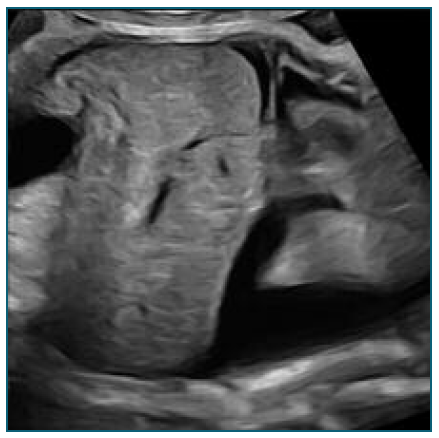

At 32 weeks (Figure 1), the fetus was found to have imaging findings consistent with fetal hydrops (bilateral pleural effusion and ascites), showing a sudden deterioration compared to the ultrasound performed at 28 weeks. Flowmetry was normal, but considering the worsening, a multidisciplinary meeting opted for hospitalization with induction of lung maturation and placement of pleuro-amniotic shunt.